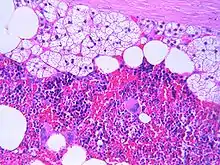

مجهريًّا

الورم الشحمي النقوي النمطي يظهر في الصورة، ويتكون من خلايا الغدة الكظرية الطبيعية وخلايا دهنية والخلايا المكوِّنة للدم بأنواعها الثلاثة: الخلايا النخاعية (المكونة لكرا الدم البيضاء)، الخلايا المكونة لكرات الدم الحمراء والخلايا المكونة للصفائح الدموية.[1]